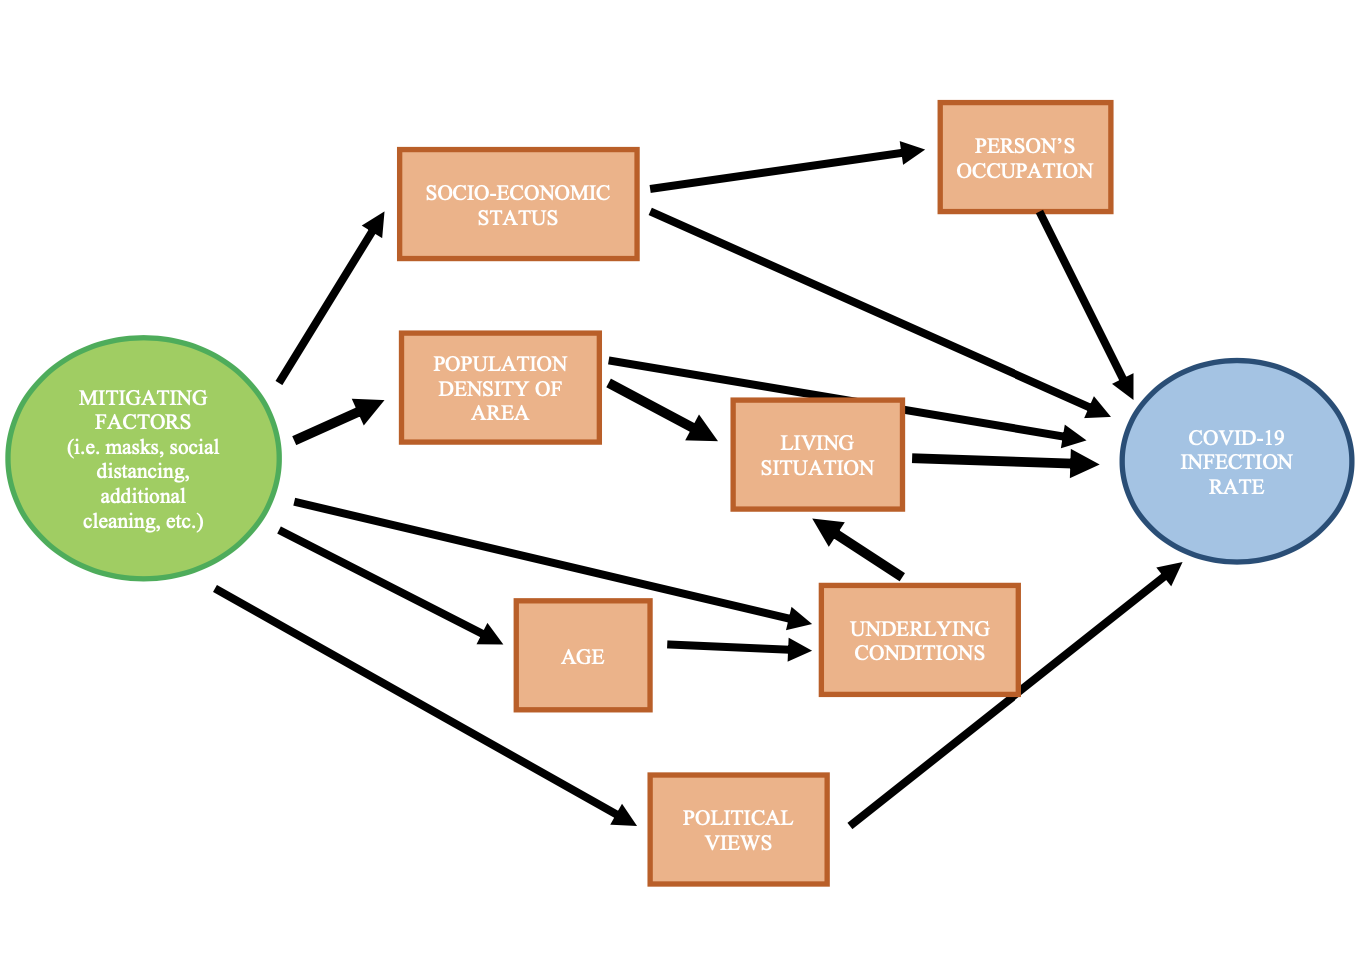

A Tour of Causal Inference through Coronavirus and Precautionary Measures

Would we have been able to stop the coronavirus pandemic potentially with different mitigating measures done earlier or would we still be in the same position we are in no matter what actions we would have taken? This project walks through the coronavirus pandemic, looking into how we could determine whether there is a causal relationship between the case numbers and mitigating measures such as social distancing, mask wearing, school closures, etc. What are some tools that we could use in order to determine how effective these measures are in preventing or slowing the spread of the virus? And what study designs make the most sense for a causal analysis of slowing the spread of the virus?